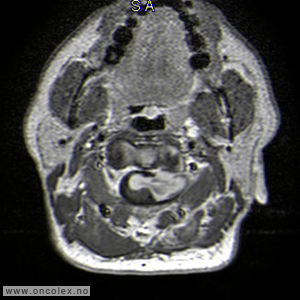

Bildediagnostiske undersøkelser

MR er det viktigste diagnostiske hjelpemiddel for å påvise svulst i ryggmargen, ryggmargsnervene og ryggmargshinnene. CT kan også brukes, men har klare begrensninger når det gjelder fremstilling av svulstene. Blant annet kan svulster som ikke tar opp kontrast bli oversett. CT og skjelettrøntgen kan imidlertid være nyttig for å kartlegge grad av skjelettødeleggelse og eventuell instabilitet i ryggsøylen.

Bildeeksempler